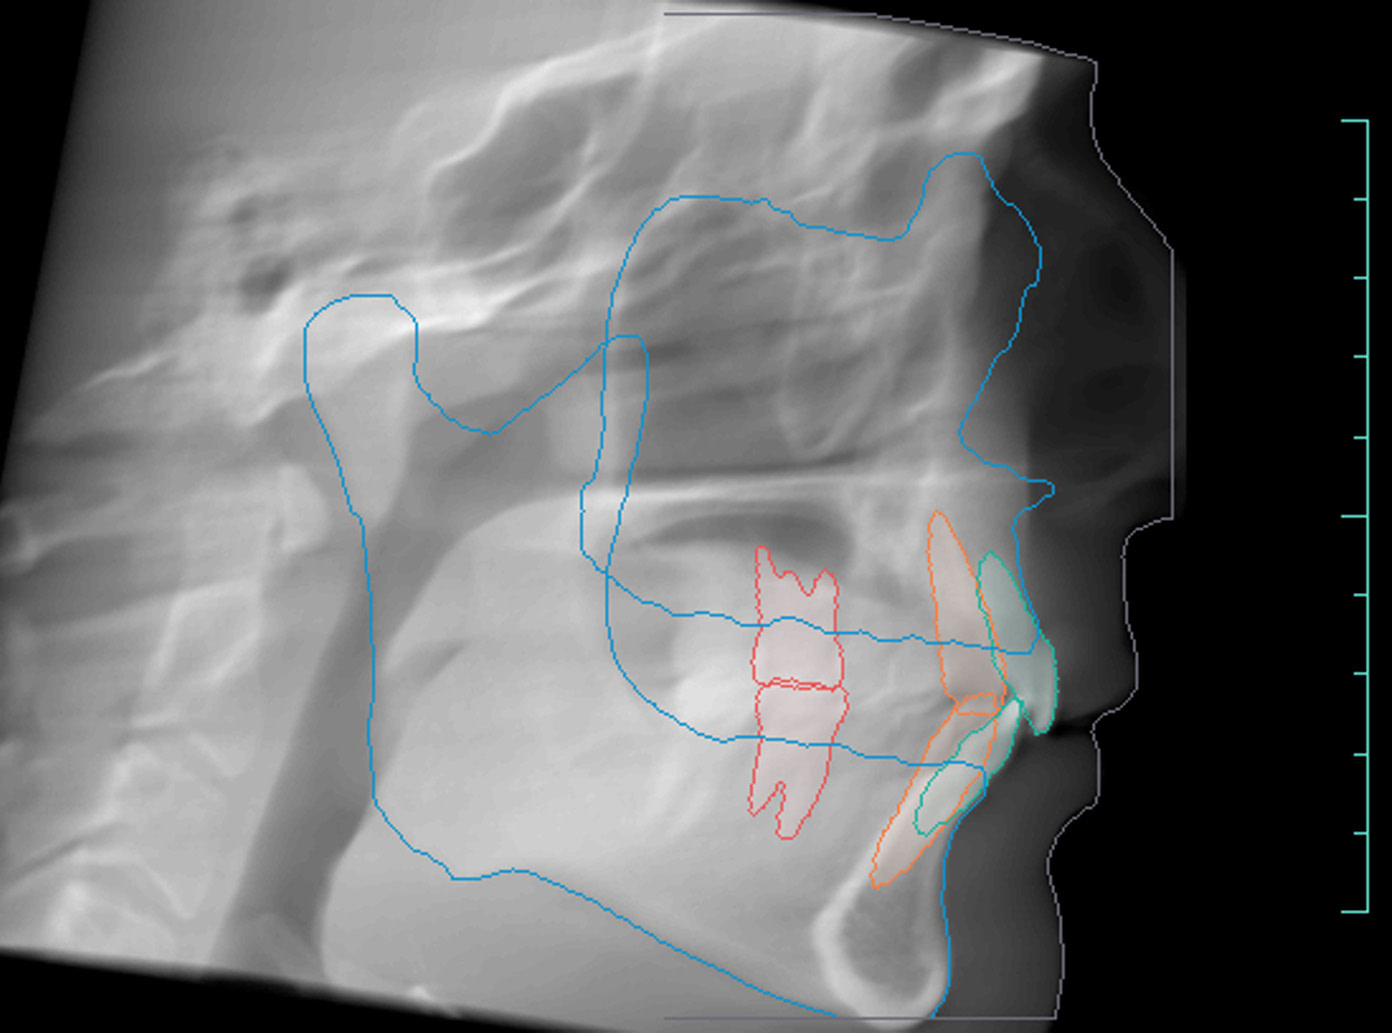

Orthodontic Report

Diagnocat is also capable of generating orthodontic reports.

This requires a CBCT radiograph with a minimum field of view of 13 x 15 x 15cm. Our Kavo OP3D machine achieves this by taking a double-field exposure and stacking two exposures on top of each other.

Diagnocat generates OPG and frontal and lateral cephalometric reconstructions from the CBCT data.

Tracings of the maxilla, mandible, central incisors, canines and molars. All automatically.

Cross-sectional and coronal views of teeth show torque and buccolingual relationships such as crossbite.

TMJ coronal/sagittal slices and summations visualize abnormal positioning/shape of the mandibular condyle.

Orthodontic, endodontic, and implantology reports are basic, with room for useful extra details.

The orthodontic report generates OPG and front/lateral cephalograms. These are not as sharp as true OPG and cephalograms. Tracings of the maxilla, mandible, central incisors, canines, and molars are automatically produced on the generated frontal/lateral cephalogram.

I showed the orthodontic report to an orthodontist colleague. She found the tracings to be fairly accurate compared to a real lateral cephalogram of the same patient. She did further tracings on the generated lateral ceph and advised it was difficult to visualize points such as Nasion, ANS, A Point, Condylion, and Orbitae and visualize the fourth vertebrae to determine peak growth phase. Furthermore, other orthodontic software can automatically calculate skeletal/dental relationships, planes, and angles.

The company did inform us that they are working on full functionality sets for orthodontic reports. This will come next year.